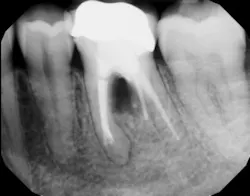

The advent of laser technology, either as an adjunct to surgical therapy or as a monotherapy, has been met with mixed results in the literature. (13) Recently, a new 9.3-micron CO2 laser (Solea from Convergent Dental) with the ability to cut both hard and soft tissue with efficiency was introduced to the dental market. This laser can penetrate deep defects with enough power to both thoroughly detoxify root surfaces and remove fibrous tissue, enhancing tissue repair (figure 2). (14) The spot size of the focal laser beam can also be controlled to a range of .25 mm to 1.25 mm so that the beam can be directed into furcation entrances. This allows previously difficult furcal defects to be detoxified prior to regenerative therapy. Because of this enhanced ability to detoxify, this laser has been able to change the prognosis of once-hopeless teeth (figure 3) and allow for tissue regeneration (figure 4) instead of extraction.

Figure 3: Tooth that would normally need to be extracted and replaced with an implant

Figure 4: Same tooth one year later after laser detoxification and periodontal regeneration with growth-stimulating factors